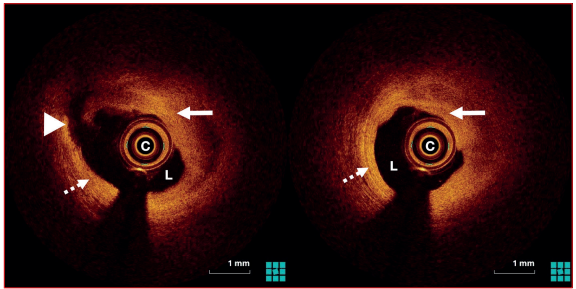

Paciente de sexo masculino, 52 años, tabaquista. Se presentó en emergencia donde se realizó diagnóstico de IAM inferoposterior Killip y Kimball I de dos horas de evolución. Se le realizó cineangiocoronariografía (CACG) de emergencia que evidenció oclusión trombótica de ramo marginal obtuso con flujo distal TIMI 1 (figura 1A). Se realizó aspiración manual del trombo y se dilató la lesión con balón. En la angiografía de control se evidenció flujo TIMI 3 y estenosis residual moderada (figura 1B). Concomitantemente se constató cese del dolor y renivelación del segmento ST. Se realizó OCT intracoronaria, en la cual se observó un extenso trombo rojo a nivel del sitio previamente ocluido (figura 2). Se inició tratamiento farmacológico con base en ácido acetilsalicílico (AAS), clopidogrel, heparina de bajo peso molecular e inhibidores de la glicoproteína IIb-IIIa. Con respecto al implante de stent, frente a la acalmia del dolor, la renivelación del segmento ST y la evidencia de trombo como principal responsable de la obstrucción, con una estenosis residual moderada, se decidió diferirlo, y esta conducta quedó supeditada a la evolución y a resultados de nuevos estudios de imagen.

Figura 1 A) Coronariografía en proyección caudal donde se observa oclusión aguda del primer ramo marginal obtuso con imagen de trombo endoluminal (flecha). B) Imagen final luego de realizar aspiración manual del trombo y dilatación con balón (flecha).

Figura 2 Imagen de OCT durante el evento coronario agudo. Cortes transversales a nivel de la lesión, donde se observa trombo endoluminal (flechas completas) que genera estenosis luminal significativa y placa aterosclerótica subyacente (flecha punteada). L: luz arterial. C: catéter.